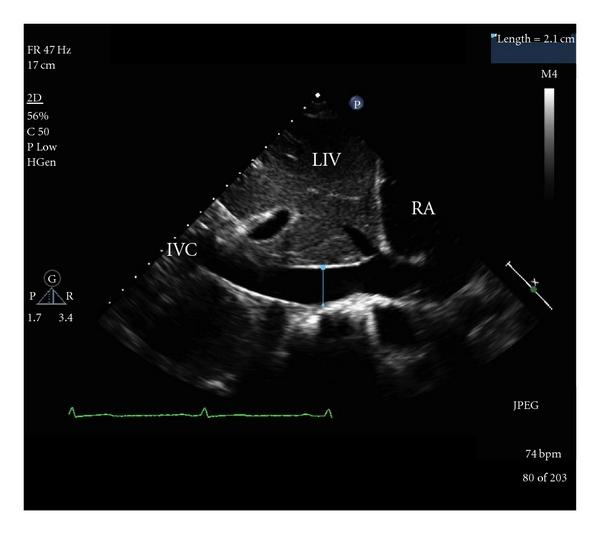

Emergency department bedside ultrasonographic measurement of the caval index for noninvasive determination of low central venous pressure.急诊床边超声测量腔静脉指数无创判断中心静脉压低。

Ann Emerg Med. 2010 Mar;55(3):290-5. doi: 10.1016/j.annemergmed.2009.04.021. Epub 2009 Jun 25.